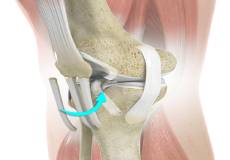

The anterior cruciate ligament (ACL) is one of the major ligaments of the knee. It is located in the middle of the knee and runs from the femur (thighbone) to the tibia (shinbone). The ACL prevents the tibia from sliding out in front of the femur. Together with the posterior cruciate ligament (PCL), it provides rotational stability to the knee.

ACL Reconstruction

ACL (anterior cruciate ligament) reconstruction is a commonly performed surgical procedure. With recent advances in arthroscopic surgery, it can now be performed with minimal incision and low complication rates.

Hamstring Autograft

ACL reconstruction with hamstring autograft method is a surgical procedure to replace the torn ACL with part of the hamstring tendon taken from your leg. The goal of ACL reconstruction surgery is to tighten your knee and restore its stability.